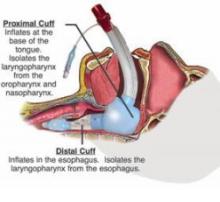

The second image shows the so called supraglottic airway device. The latest design is penis shaped:

But there are others: